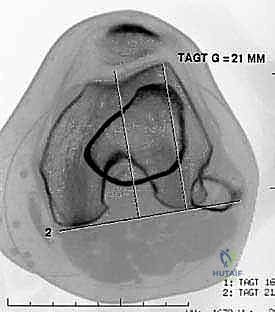

FIG 2D. Measurement of the tibial tuberosity–trochlear groove (TT-TG) offset, the transverse distance between the apex of the anterior tibial tuberosity and the center of the trochlear groove. Measurements are made on superimposed axial CT or MRI images.

<figure class="operative-step-slider my-4 text-center p-3 border rounded shadow-sm bg-light">